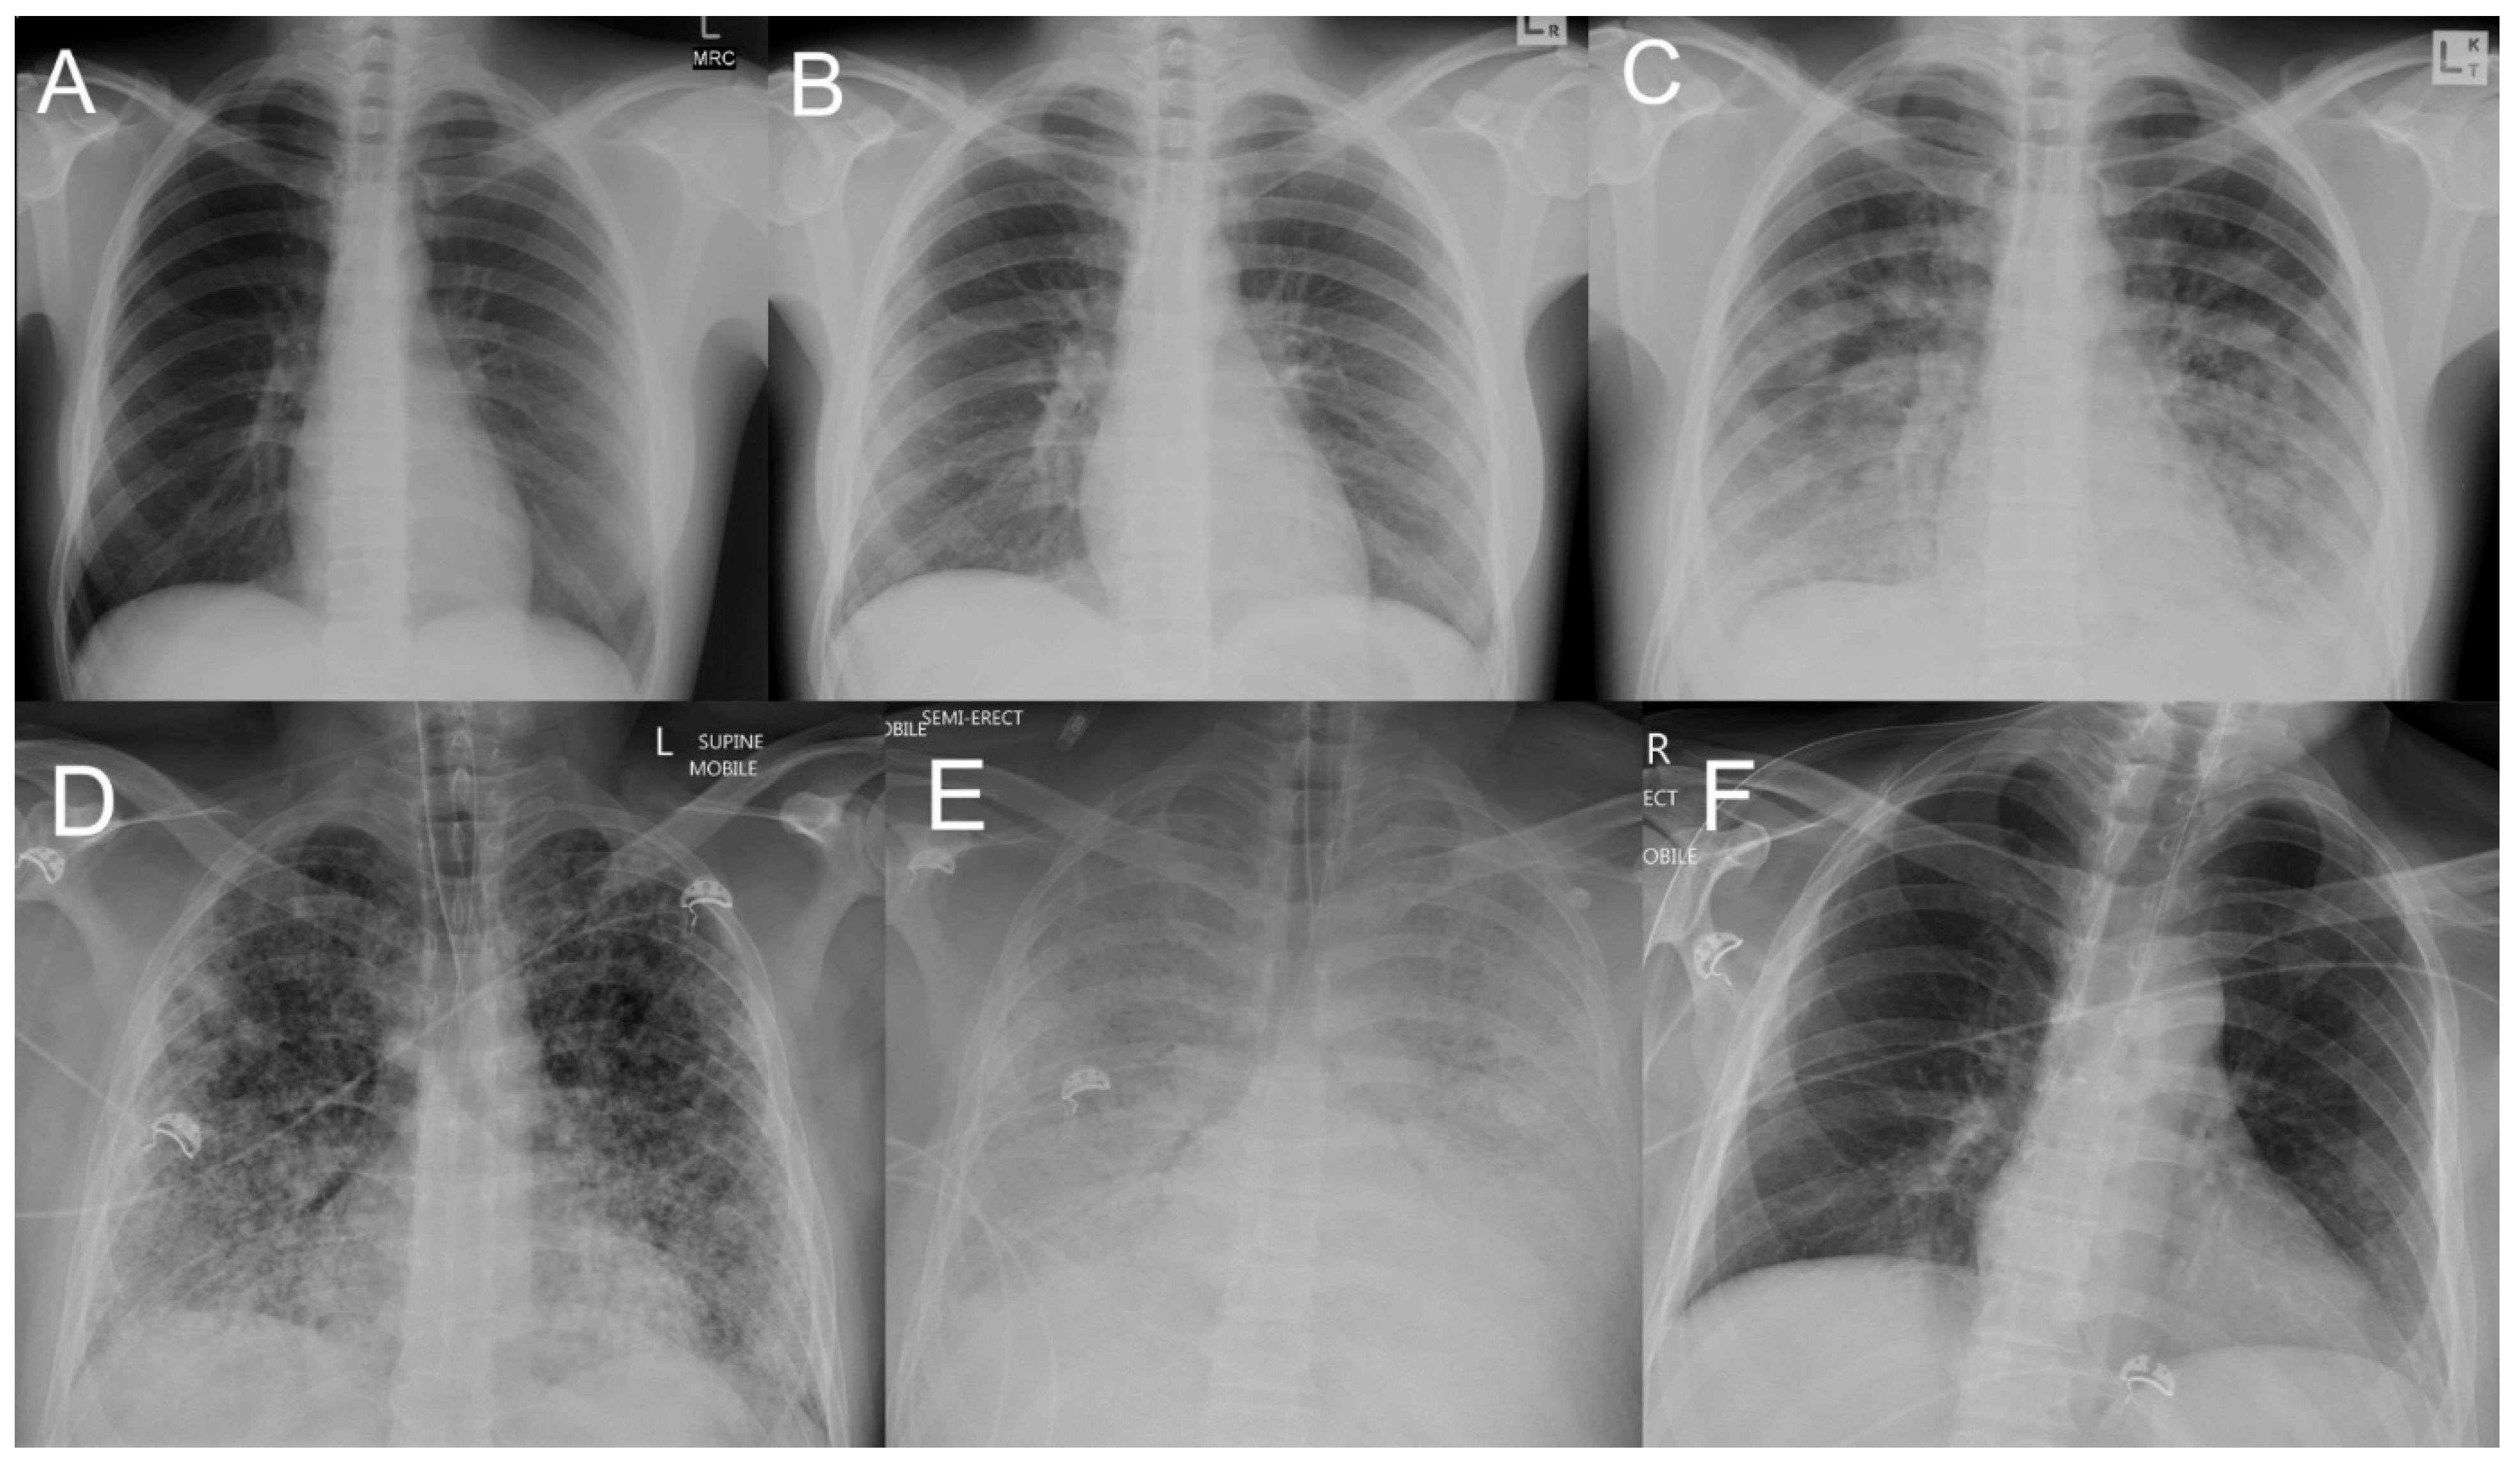

3.2. Pulmonary Haemorrhage

- Matos, E.D.; Costa, E.; Sacramento, E.; Caymmi, A.L.; Neto, C.A.; Barreto Lopes, M.; Lopes, A.A. Chest radiograph abnormalities in patients hospitalized with leptospirosis in the city of Salvador, Bahia, Brazil. Braz. J. Infect. Dis. 2001, 5, 73–77. [Google Scholar] [CrossRef]

- Tanomkiat, W.; Poonsawat, P. Pulmonary radiographic findings in 118 leptospirosis patients. Southeast Asian J. Trop. Med. Public Health 2005, 36, 1247–1251. [Google Scholar] [PubMed]

- Marchiori, E.; Lourenço, S.; Setúbal, S.; Zanetti, G.; Gasparetto, T.D.; Hochhegger, B. Clinical and imaging manifestations of hemorrhagic pulmonary leptospirosis: A state-of-the-art review. Lung 2011, 189, 1–9. [Google Scholar] [CrossRef]